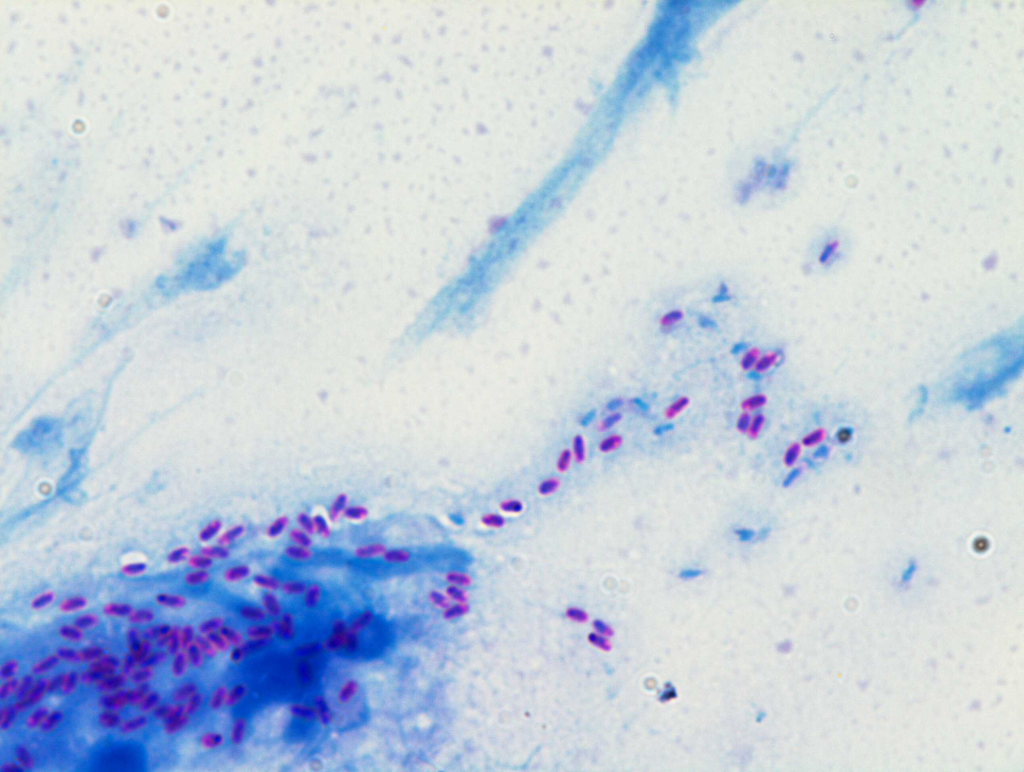

Media routinely used in ocular microbiology media are routinely used in ocular microbiology are:- Blood agar (BA), Chocolate agar (CA), Sabouraud dextrose agar (SDA), Nutrient agar (NA), Non-nutrient agar (NNA) with E. coli overlay, and Thioglycollate broth.

Blood Agar is preferred in ocular samples because it supports a wide range of bacteria, including Gram-positive cocci, and helps detect hemolysis, which is useful for differentiation

the purpose of Chocolate Agar in eye infections is to supports growth of fastidious organisms such as Haemophilus influenzae and Neisseria gonorrhoeae,important ocular pathogens

Enrichment media enhance the growth of pathogens when present in small numbers. Example: Brain Heart Infusion Broth or Thioglycollate broth for intraocular fluids.

Solid media help isolate colonies and observe morphology, while liquid media enhance growth from low inoculum or sterile-site samples.

It is used to detect Acanthamoeba, a protozoan causing severe keratitis, especially in contact lens users.

Different microorganisms have varied nutritional needs. Using selective, differential, enriched, and specialized media allows accurate isolation, identification, and study of diverse bacteria, fungi.

Selective media inhibit unwanted microbes and allow target organisms (e.g., MacConkey agar for Gram-negative bacilli). Differential media distinguish between organisms based on biochemical reactions